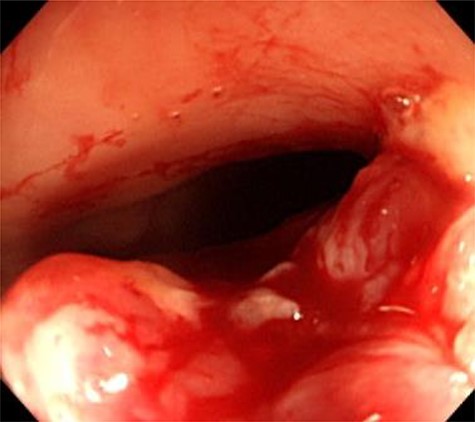

Colonoscopy findings. Colonoscopy showed a malignant tumor of the rectum. The tumor was localized, and invasion outside the colonic wall was suspected.

the uterus and rectum (Fig. 2A). The computed tomography scan showed expansion of the intestines and no evidence of free intraperitoneal air (Fig. 2B). As she had a history of bloody stool and the CEA level was increased, we performed colonoscopy, which showed a malignant tumor of the rectum (Fig. 3). The protruding tumor was located 7 cm from the anus. Exploratory laparotomy showed a 90-mm pelvic mass involving the uterus, ileum and rectum. Therefore, we performed an en bloc resection of the mass, including total hysterectomy, bilateral salpingo-oophorectomy, partial resection of the ileum and the Hartmann operation. Macroscopically, the resected pelvic mass invaded the uterus, intestine and rectum, and a colouterine fistula was identified (Fig. 4). The main portion of the tumor was located in the rectum, and it grossly appeared that tumor invasion occurred from the rectum to the uterus and ileum. Microscopic examination of the pelvic mass showed complicated glandular structures in a desmoplastic stroma. The cells forming the lumen were primarily columnar epithelium, consistency of the small glandular cavity was high and severe dyskaryotic cells were multilayered. The nuclei were enlarged and irregularly shaped, contained coarse chromatin and showed atypia. Immunohistochemical staining was performed. Cytokeratin (CK)20 (Dako), NCL-Villin (Novocastra) and CEA (Dako) were positive, and CK7 (Dako) was negative. The final diagnosis was moderately differentiated tubular adenocarcinoma of the rectum, stage IIC, pT4b N0 M0. The patient’s postoperative course was uneventful. The serum level of CEA returned within normal range 1 month postoperatively. Adjuvant chemotherapy (TS-1) was administered for 6 months postoperatively. The patient has been followed up with for >12 months without any signs of recurrence.